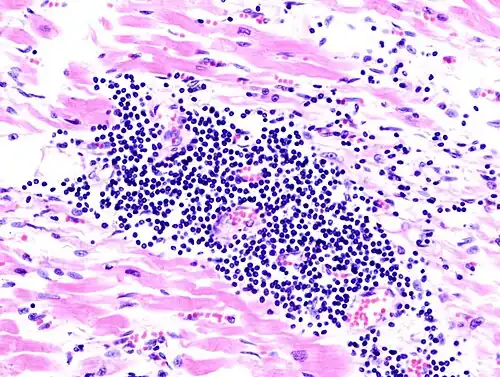

| A microscope image of myocarditis at autopsy in a person with acute onset of heart failure. The black dots are primarily lymphocytes infiltrating the myocardium. | |

Most forms of myocarditis involve the infiltration of heart tissues by one or two types of pro-inflammatory blood cells, lymphocytes and macrophages plus two respective descendants of these cells, NK cells and macrophages. Eosinophilic myocarditis is a subtype of myocarditis in which cardiac tissue is infiltrated by another type of pro-inflammatory blood cell, the eosinophil. Eosinophilic myocarditis is further distinguished from non-eosinophilic myocarditis by having a different set of causes and recommended treatments.[36][20]

The gold standard is the biopsy of the myocardium, in general done in the setting of angiography. A small tissue sample of the endocardium and myocardium is taken and investigated. The cause of the myocarditis can be only identified by a biopsy. Endomyocardial biopsy samples are assessed for histopathology (how the tissue looks like under the microscope): myocardial interstitium may show abundant edema and inflammatory infiltrate, rich in lymphocytes and macrophages. Focal destruction of myocytes explains the myocardial pump failure.[12] In addition samples may be assessed with immunohistochemistry to determine which types of immune cells are involved in the reaction and how they are distributed. Furthermore, PCR and/or RT-PCR may be performed to identify particular viruses. Finally, further diagnostic methods like microRNA assays and gene-expression profile may be performed.